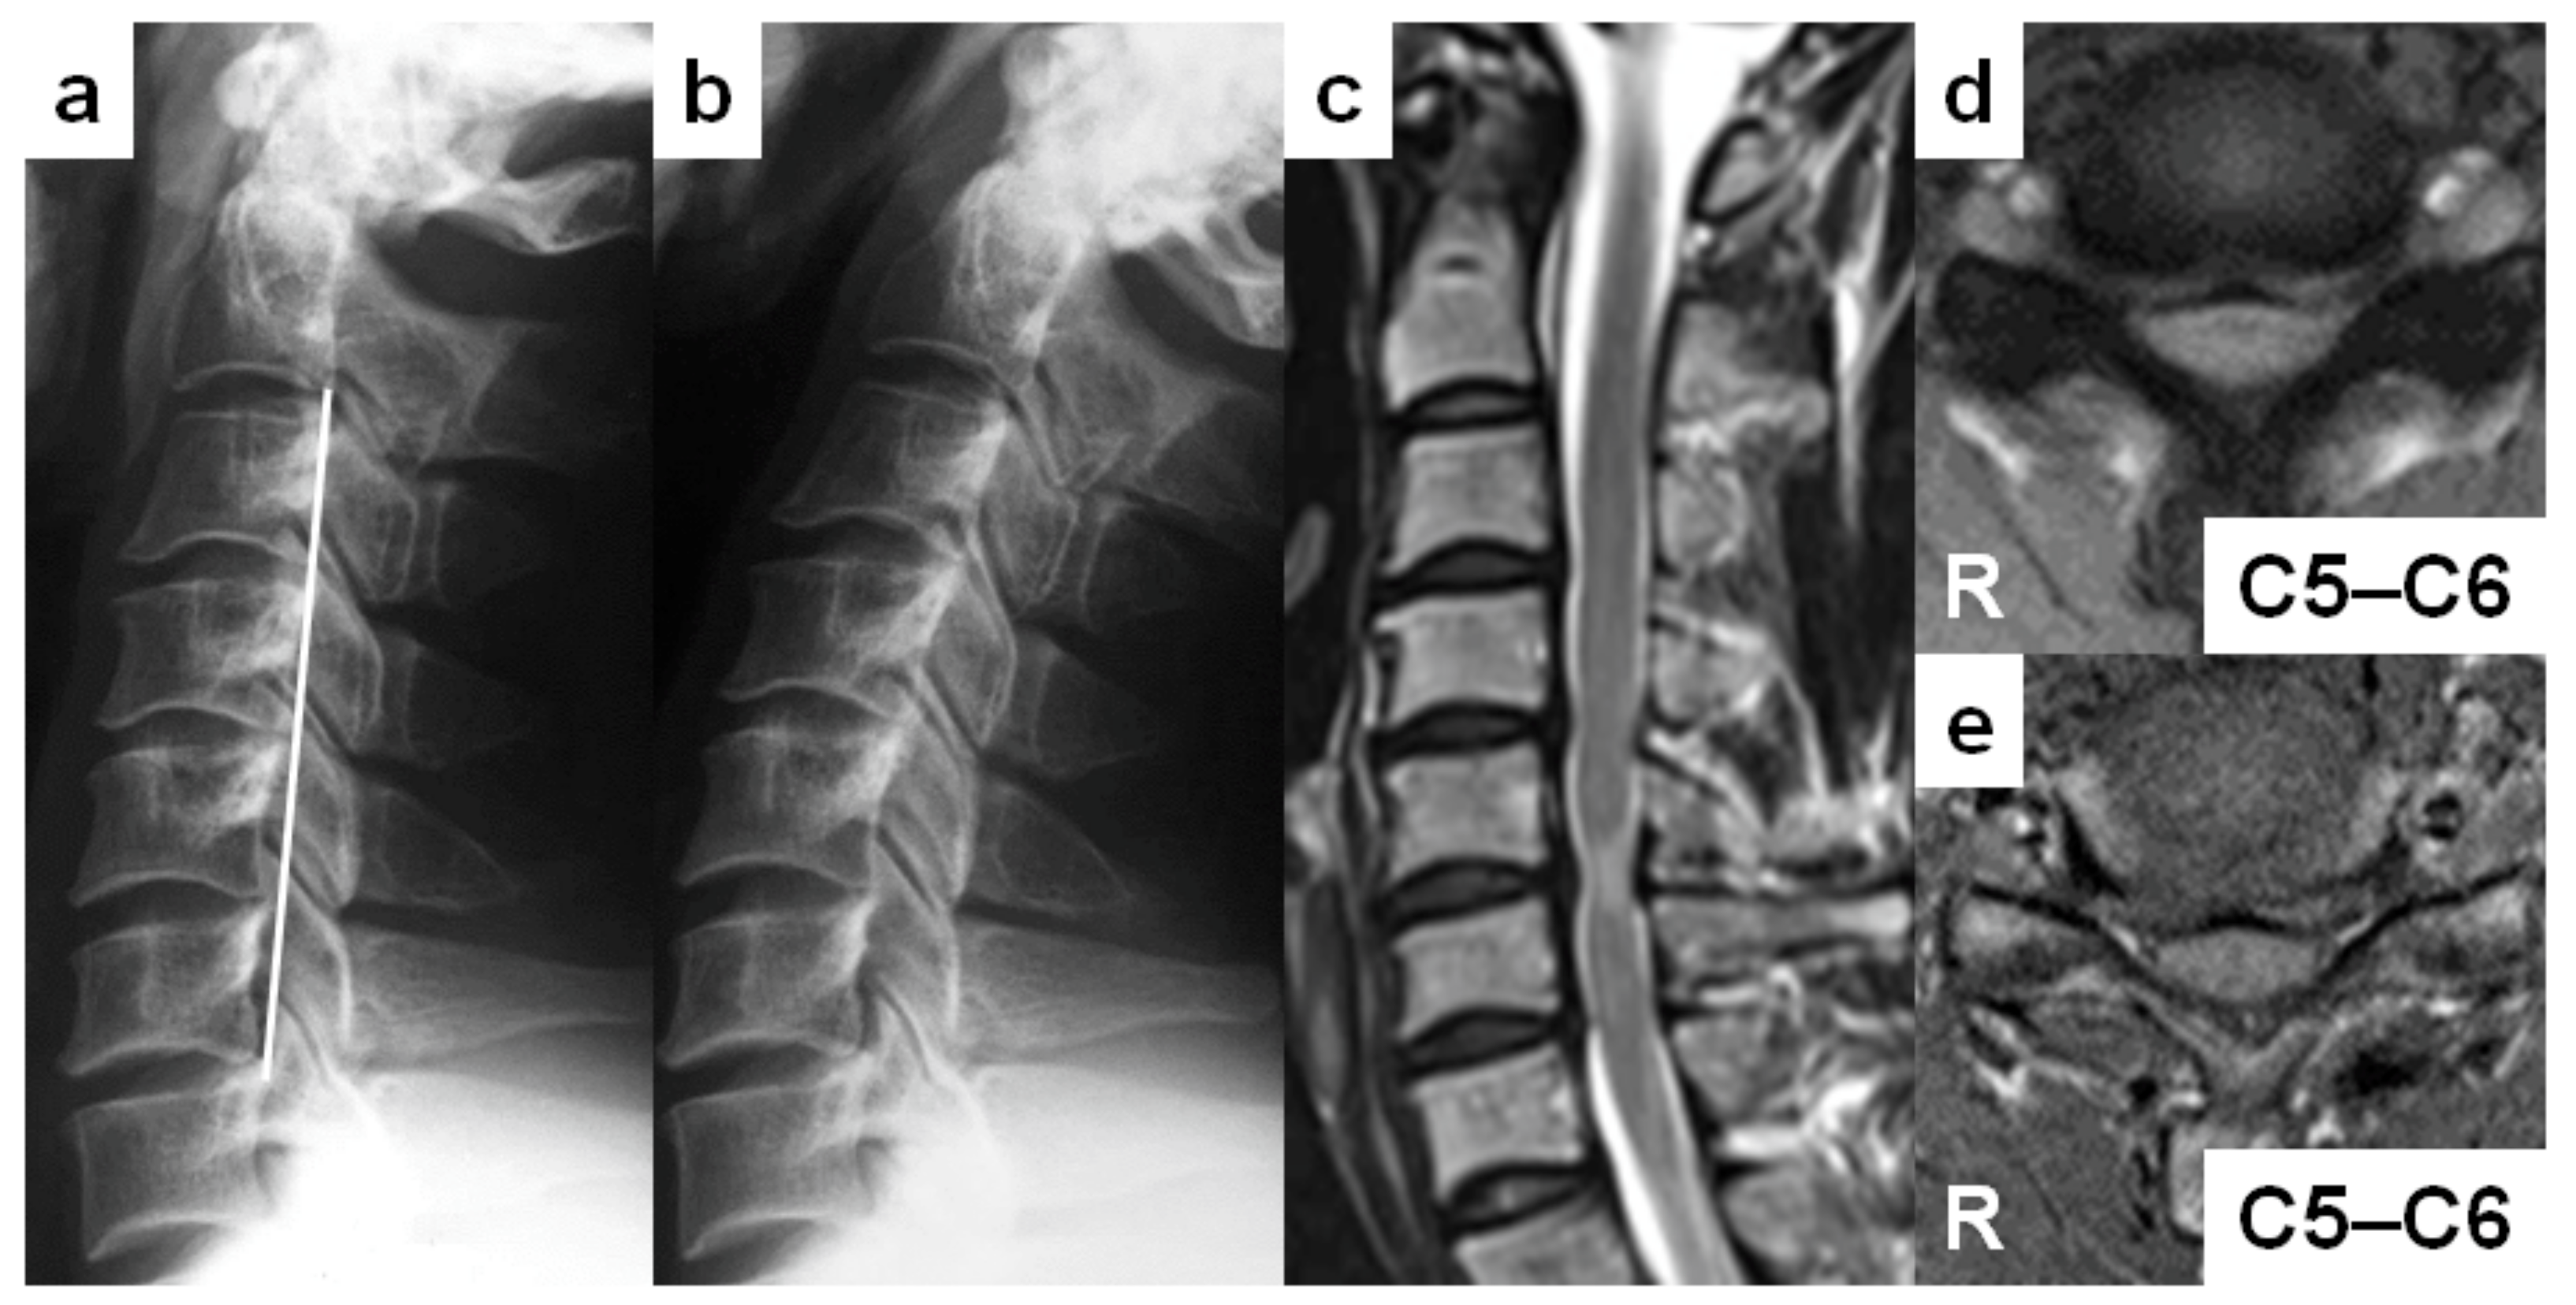

A 24-year-old man (case no. 3)’s complaint was right finger numbness when the neck was extended. He had no sports activities but was a pastry chef requiring frequent neck extension. He demonstrated the negative Romberg sign, normal deep tendon reflexes, and modest sensory disturbance on his right finger with 16 of 17 points in the JOA score. His cervical sagittal alignment was “reverse sigmoid” (Figure 3a). The Torg–Pavlov ratio was positive from C3 to C7, although the DVF was negative throughout. Positive DNF at C4–C5 level and posterior vertebral slip at C4 were found in full-extension position (Figure 3b). “Degenerative” discs existed from C3–C4 to C6–C7 (Figure 3c). There was no signal hyperintensity on T2-weighted MRIs, but the positive spinal cord compression was seen at C4–C5 (Figure 3c,d). On T1-weighted MRIs, “ovoid” spinal cord deformity was shown at the neurologically responsible segment of C4–C5 (Figure 3e). No foraminal stenosis or peripheral nerve disorder were detected. After C4–C5 anterior cervical discectomy and fusion, his neurological condition had a full recovery one year after surgery.

Figure 3. Report of a 24-year-old man with cervical spondylotic myelopathy (case no. 3). (a,b) Lateral cervical spine radiographs in neutral (a) and full-extension (b) positions demonstrating the “reverse-sigmoid” sagittal cervical alignment and posterior vertebral slip at C4. (c) A sagittal T2-weighted magnetic resonance image (MRI) demonstrating “degenerative” discs from C3–C4 to C6–C7, spinal cord compression at C4–C5, and no intramedullary increased signal intensity lesions. (d) An axial T2-weighted MRI demonstrating the narrowed cervical spinal canal without any intramedullary increased signal intensity areas at C4–C5. (e) An axial T1-weighted MRI demonstrating the “ovoid” spinal deformity at C4–C5.